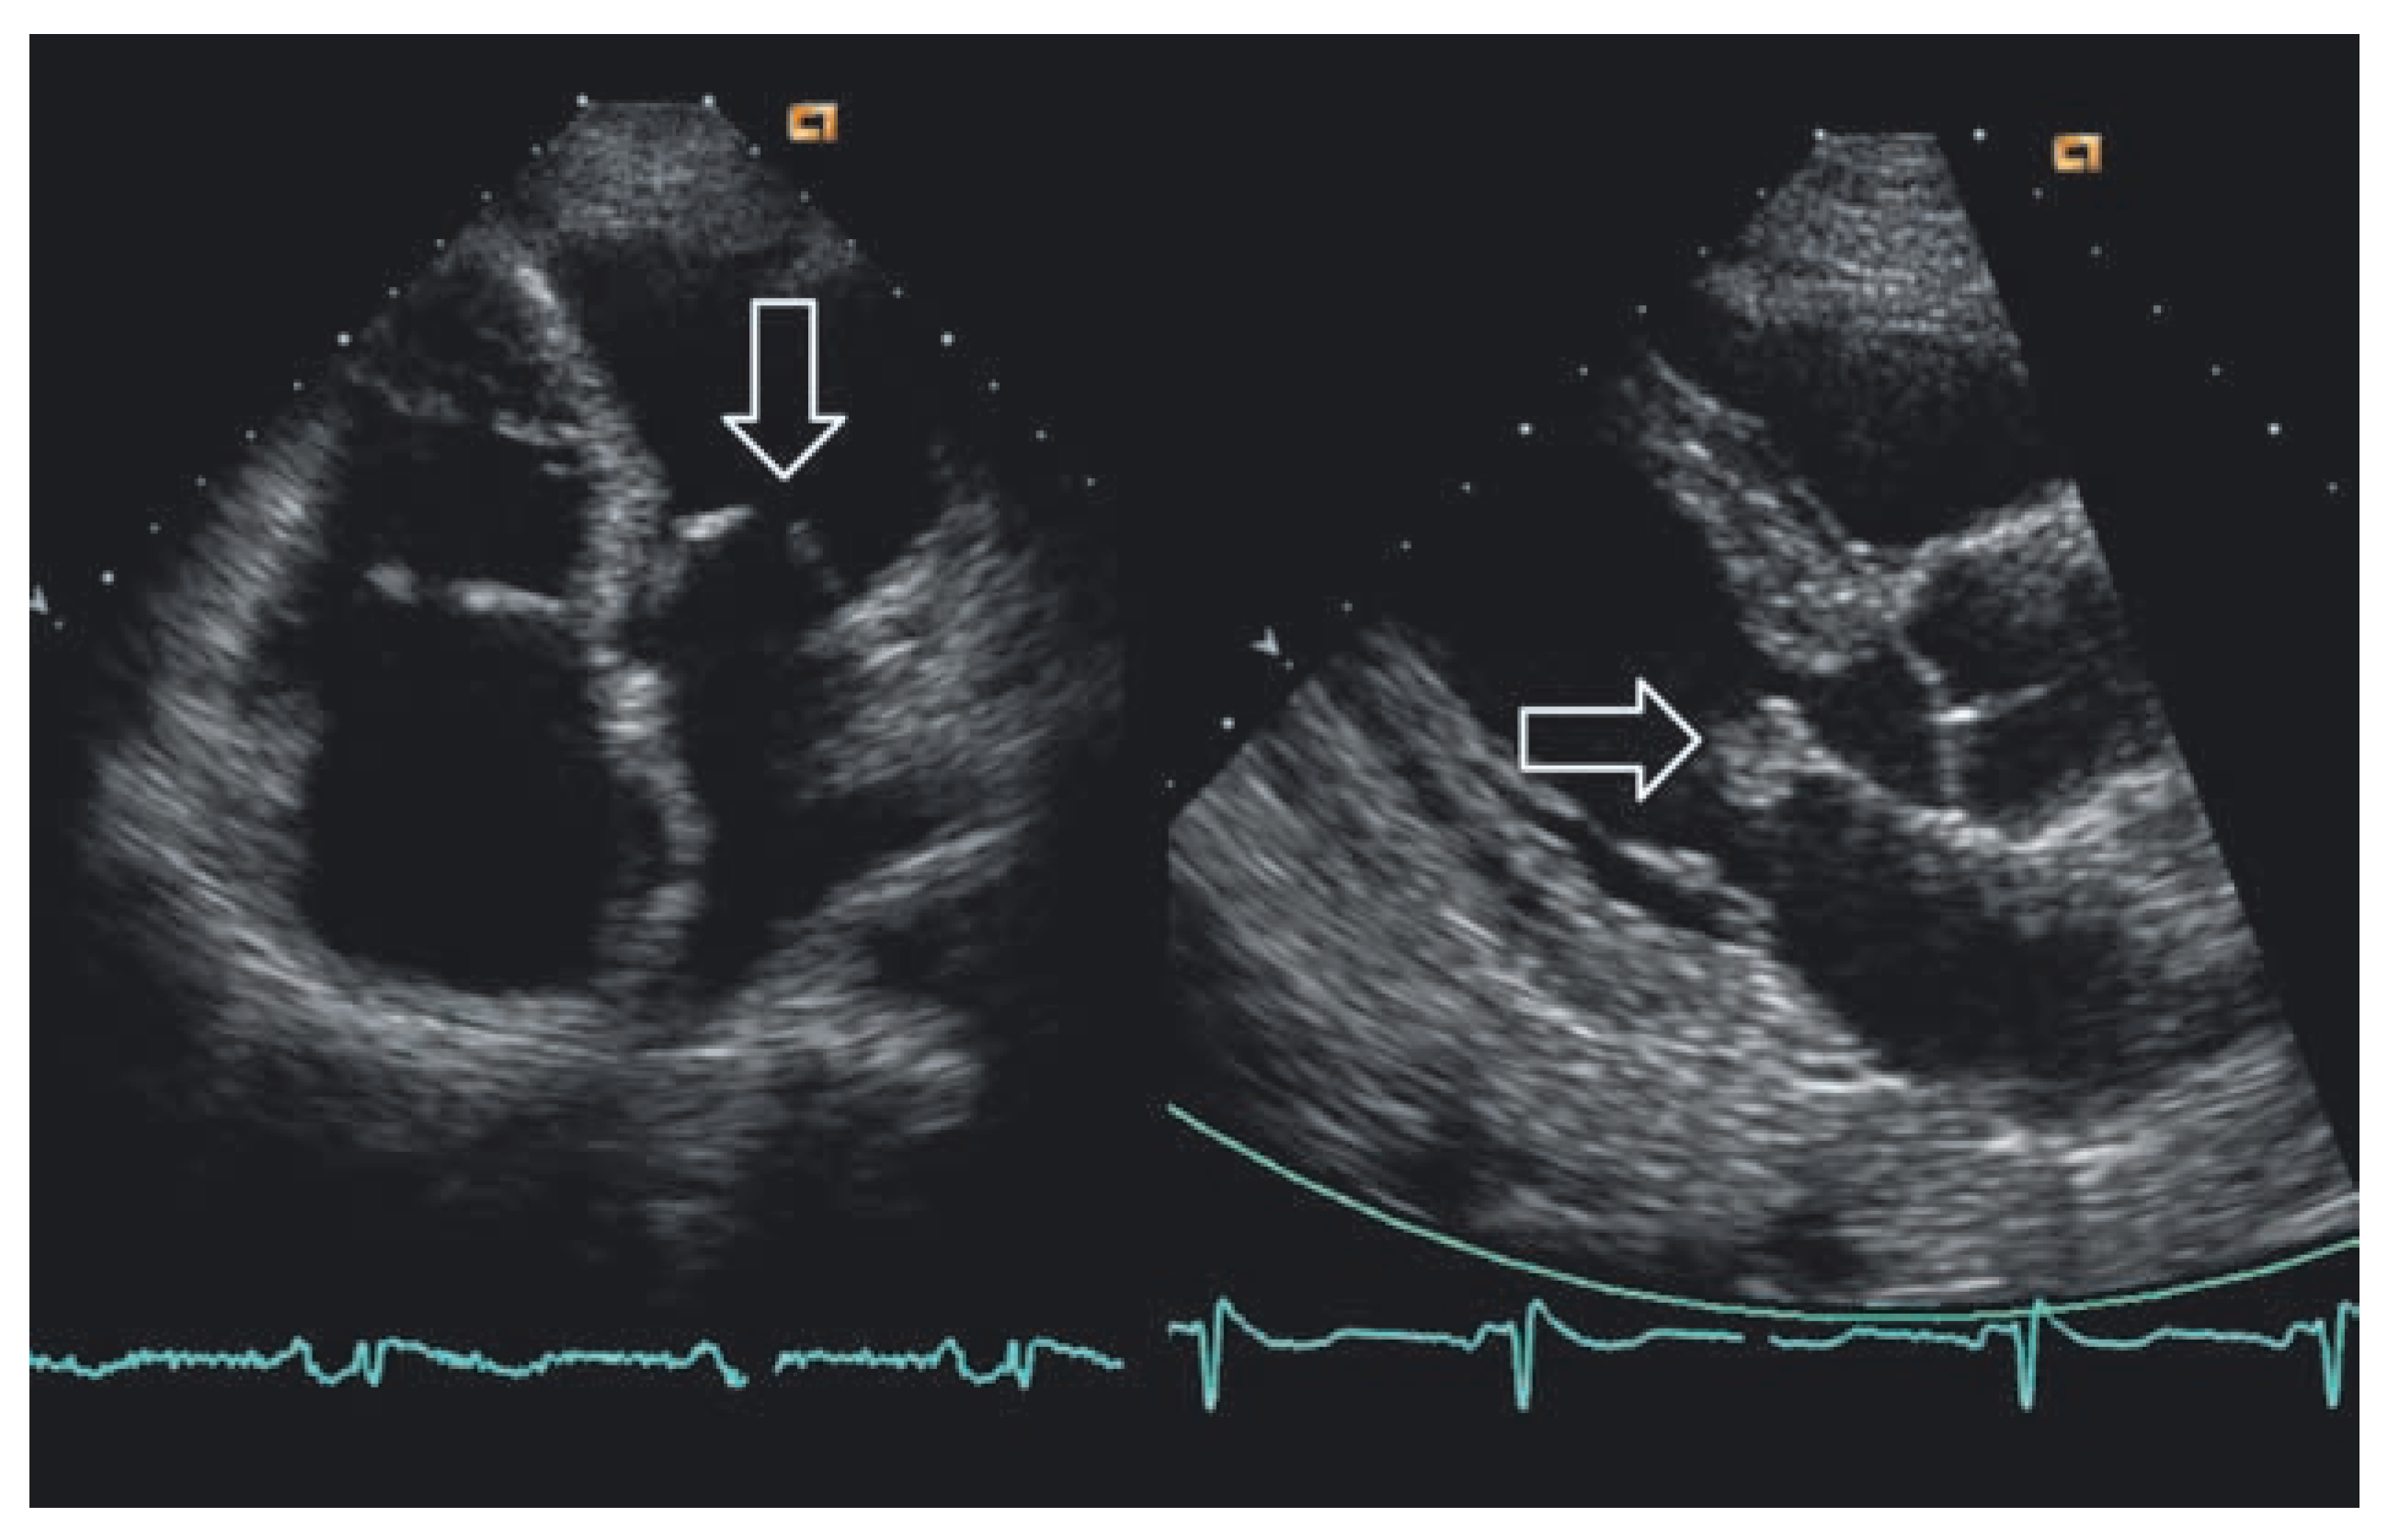

Abbildung 2. Echokardiographischer Befund bei post-rheumatischer Mitralstenose (links) und bei Mitralklappen-endokarditis mit Auflagerungen auf dem vorderen Mitralsegel (rechts).

Als im Juli 1907 die Tochter Maria in Maiernigg verstarb und seine Frau Alma ohnmächtig daniederlag, bat Mahler den herbeigeholten Doktor Blumenthal, doch auch noch auf sein Herz zu hören. Der Landarzt meinte lakonisch: «Na, auf dieses Herz brauchen Sie aber nicht stolz zu sein.» Mahler liess sich tief beunruhigt in Wien vom bekannten Herzspezialisten Professor Kovacs untersuchen, der einen angeborenen, kompensierten Herzfehler diagnostizierte. Ein weiterer Wiener Arzt, Doktor Hamperl, legte sich dann aufgrund des Auskultationsbefundes auf die Diagnose Mitralstenose fest (Abb. 2, links).

Wie kam Lipman zu dieser Diagnose? Gewiss, an Fachwissen fehlte es ihm nicht – schliesslich wurde er aufgrund der nach ihm benannten ungewöhnlichen, aber im Falle von Mahler nicht vorliegenden Form einer Herzklappenentzündung später eine medizinische Berühmtheit – doch wie ging er vor? Wie konnte er wiederkehrendes Fieber, die seit Jahren auftretenden Anginen, Hautblutungen, ein Herzgeräusch, das damals wohl so häufig war wie die übrigen Befunde, zur Diagnose fügen? Zweifellos musste er das Krankheitsbild als solches kennen; nur auf dem Hintergrund dieses unscharfen, aber leitenden Bildes konnte er zu einem Urteil gelangen. Bei der Endokarditis zeigt sich, was klinisches Denken umfasst, nämlich das Zusammenfügen einzelner Befunde wie Fieber, Müdigkeit und Unwohlsein, die ebenso zu einer alltäglichen Grippe wie zur gefürchteten Endokarditis gehören können, sowie heftiger Temperaturschübe, eines neuen Herzgeräuschs und einiger Laborbefunde wie Senkungsreaktion, Anämie, Leukozytose. Damit sollte man zur Diagnose oder doch zu einer working hypothesis geführt werden. Keiner der Befunde für sich alleine ist leitend, erst ihre Verbindung lässt den Arzt weiterkommen. Im Falle der Endokarditis kann Schüttelfrost dazukommen, der auf eine Bakteriämie weist. Eine Vergrösserung der Milz, ebenso wie punktförmige Blutungen der Bindehaut und der Fingerkuppen (Abb. 3) führten Lipman möglicherweise weiter. Richtig beunruhigend war all dies bei einem Patienten mit vorgeschädigten Herzklappen, einem Locus minoris resistentiae, wie geschaffen für Bakterien, um sich darin einzunisten und sich der natürlichen Körperabwehr zu entziehen. Das Herzgeräusch war seit Jahren bekannt und daher nicht sicher einzuordnen; möglich, dass es damals besonders eindrücklich zu hören war, zum einen wegen der typischen Blutarmut dieser Patienten, zum anderen aufgrund der Auflagerungen auf der kranken Klappe (Abb. 2, rechts) – es waren also eine Reihe von Beschwerden und Befunden, die den Arzt zur Diagnose führte.